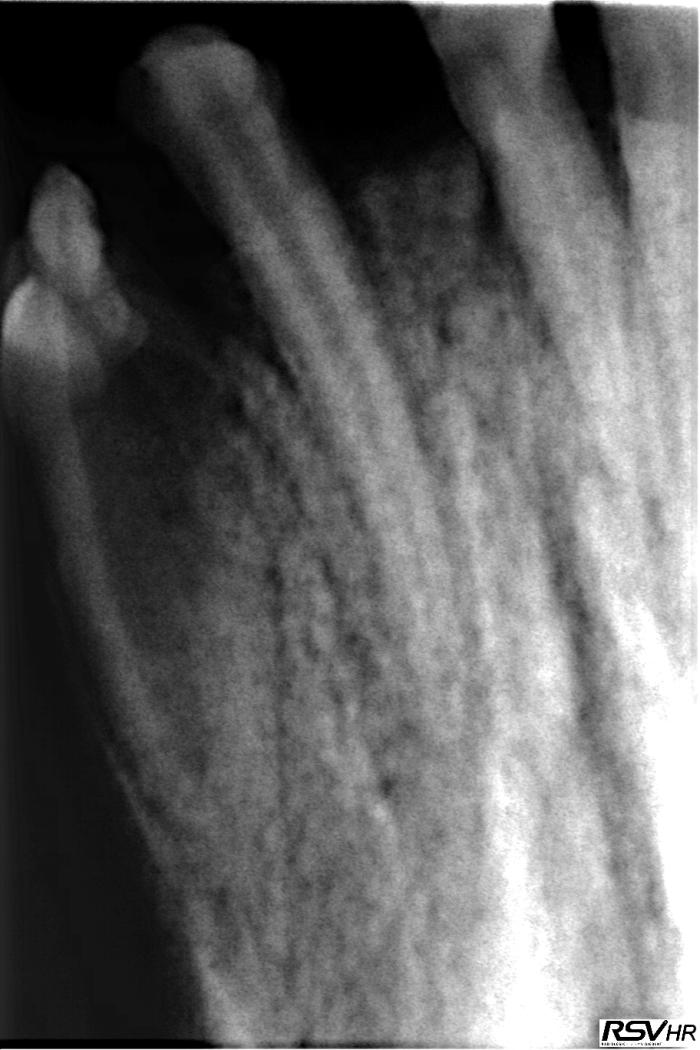

A continuación, se sometió al paciente a sedación profunda para realizar una exploración más completa y un estudio radiográfico intraoral. Además de confirmarse la ausencia externa de 401 y 404, en la exploración se observaron con mayor detenimiento las irregularidades del diente 403 (Figuras 1 y 2), presentando lobulaciones e invaginación en la corona (pliegues anormales del esmalte hacia el interior del diente).

El estudio radiográfico intraoral reveló diversas alteraciones:

- Ausencia completa o agenesia del diente 401 (Figura3).

- Tamaño más pequeño de lo normal, o microdoncia, del diente 402 (ver Figura 3).

- Invaginación y radiolucidez periapical, sugiriendo infección, del diente 403 (ver Figura 3) (Figura4).

- Presencia del diente 404, incluido en el cuerpo mandibular, ventral a los dientes 406 y 407, con una forma acortada y aberrante (Figuras 5-7).

- Fusión de las raíces del diente 406, sin signos patológicos asociados (ver Figura 5).